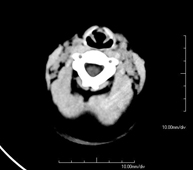

Prueba radiológica que consiste en obtener imágenes del cráneo de alta definición anatómica (tronco cerebral, cerebelo, cerebro, calota craneal, etc.), mediante el empleo de un equipo de TC (Tomografía Computarizada).Indicaciones: traumatismos, cefalea, trastornos de la memoria, pérdida de fuerza súbita en una extremidad o mitad del cuerpo. - TC Cuello